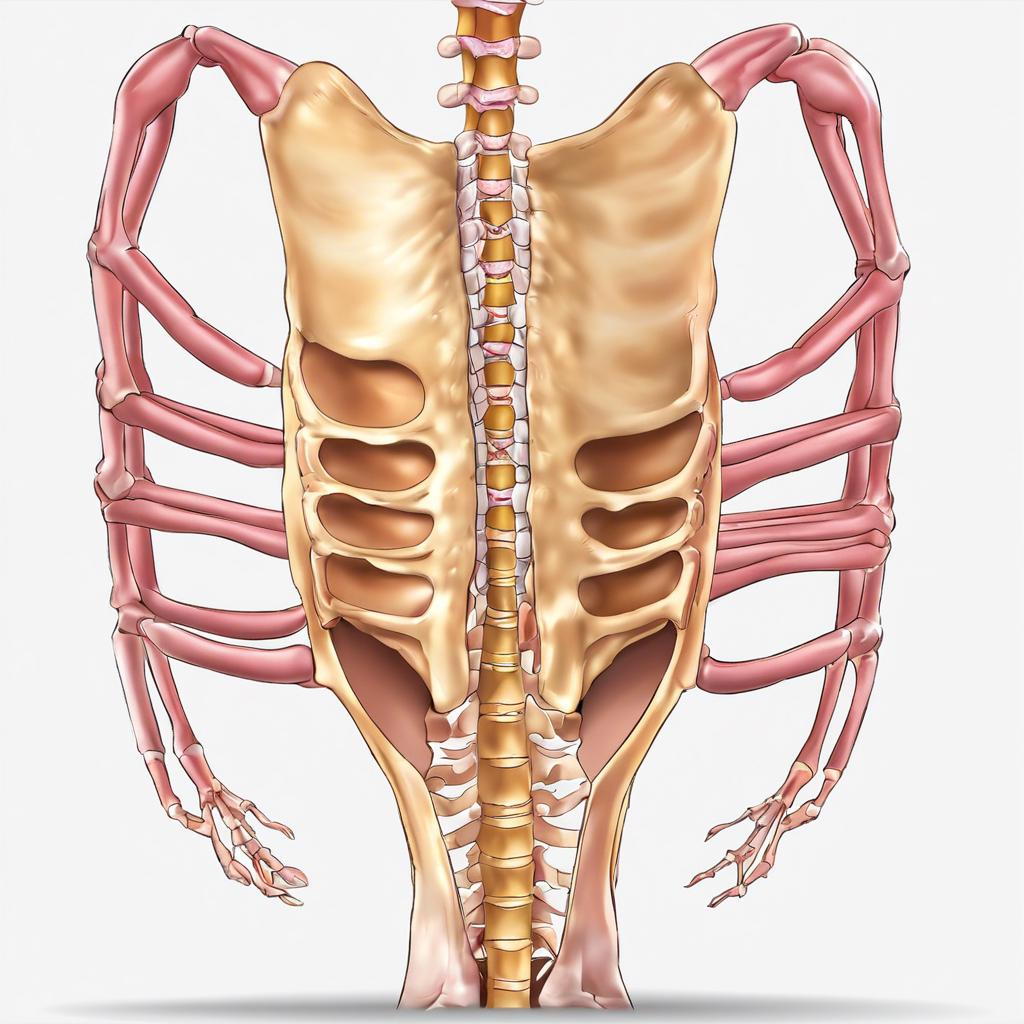

A herniated disk can sound intimidating, but understanding it doesn't have to be. This common spinal condition affects millions of people each year and can lead...